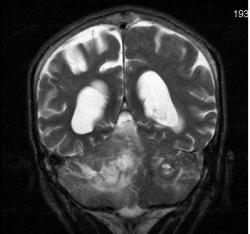

Мужчина 73 лет. За последний год похудел, потерял аппетит. Последний месяц стал плохо ходить, несколько раз падал, неделю назад стал психически не совсем адекватен. Врач - друг семьи, приехавший в гости, настоял на проведении МРТ головного мозга, рентгенографии ОГК и УЗИ брюшной полости. МРТ проводилось в медикаментозном сне, с реанимационным набором наизготовку, по немного укороченным программам. Все закончилось благополучно. Ничего сложного в плане диагностики. Просто не всегда бывает так много и ярко. Есть небольшое продолжение. Потом.

Т2 фронтальные сканы:

метастазы